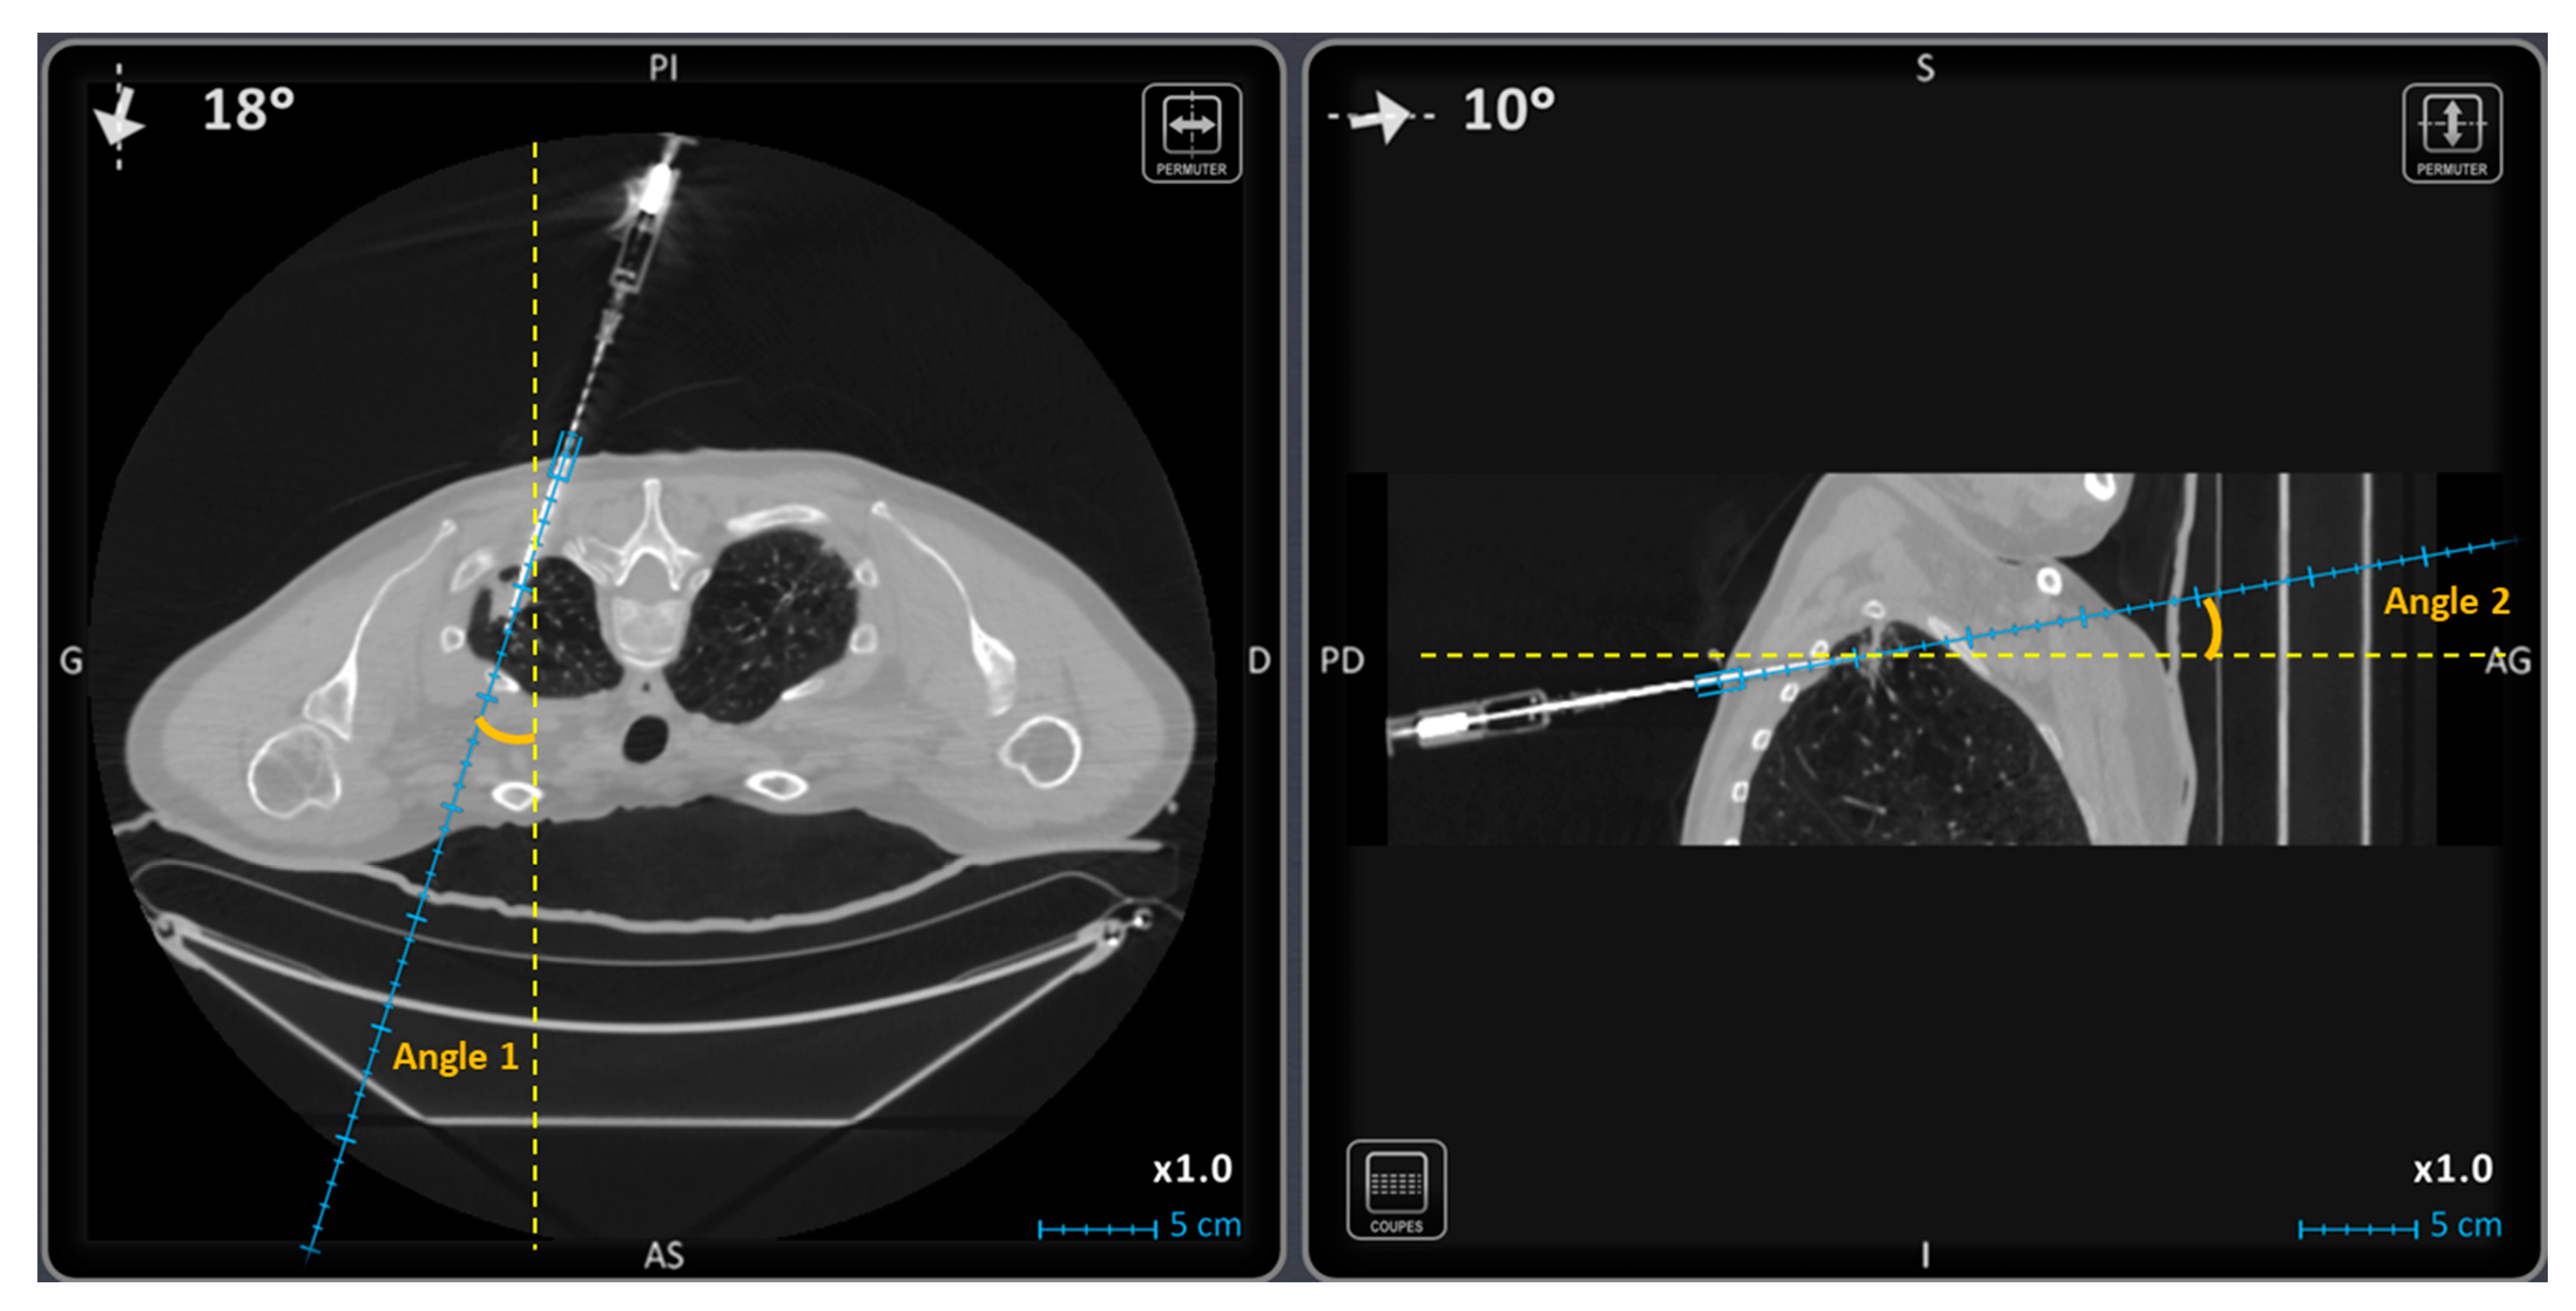

| Trajectory angle 1 (°) | 15.5 [3.0; 31.5] | 6.0 [2.0; 13.0] | 0.0008 |

| Trajectory angle 2 (°) | 10.0 [3.0; 16.3] | 1.0 [1.0; 5.0] | <0.0001 |